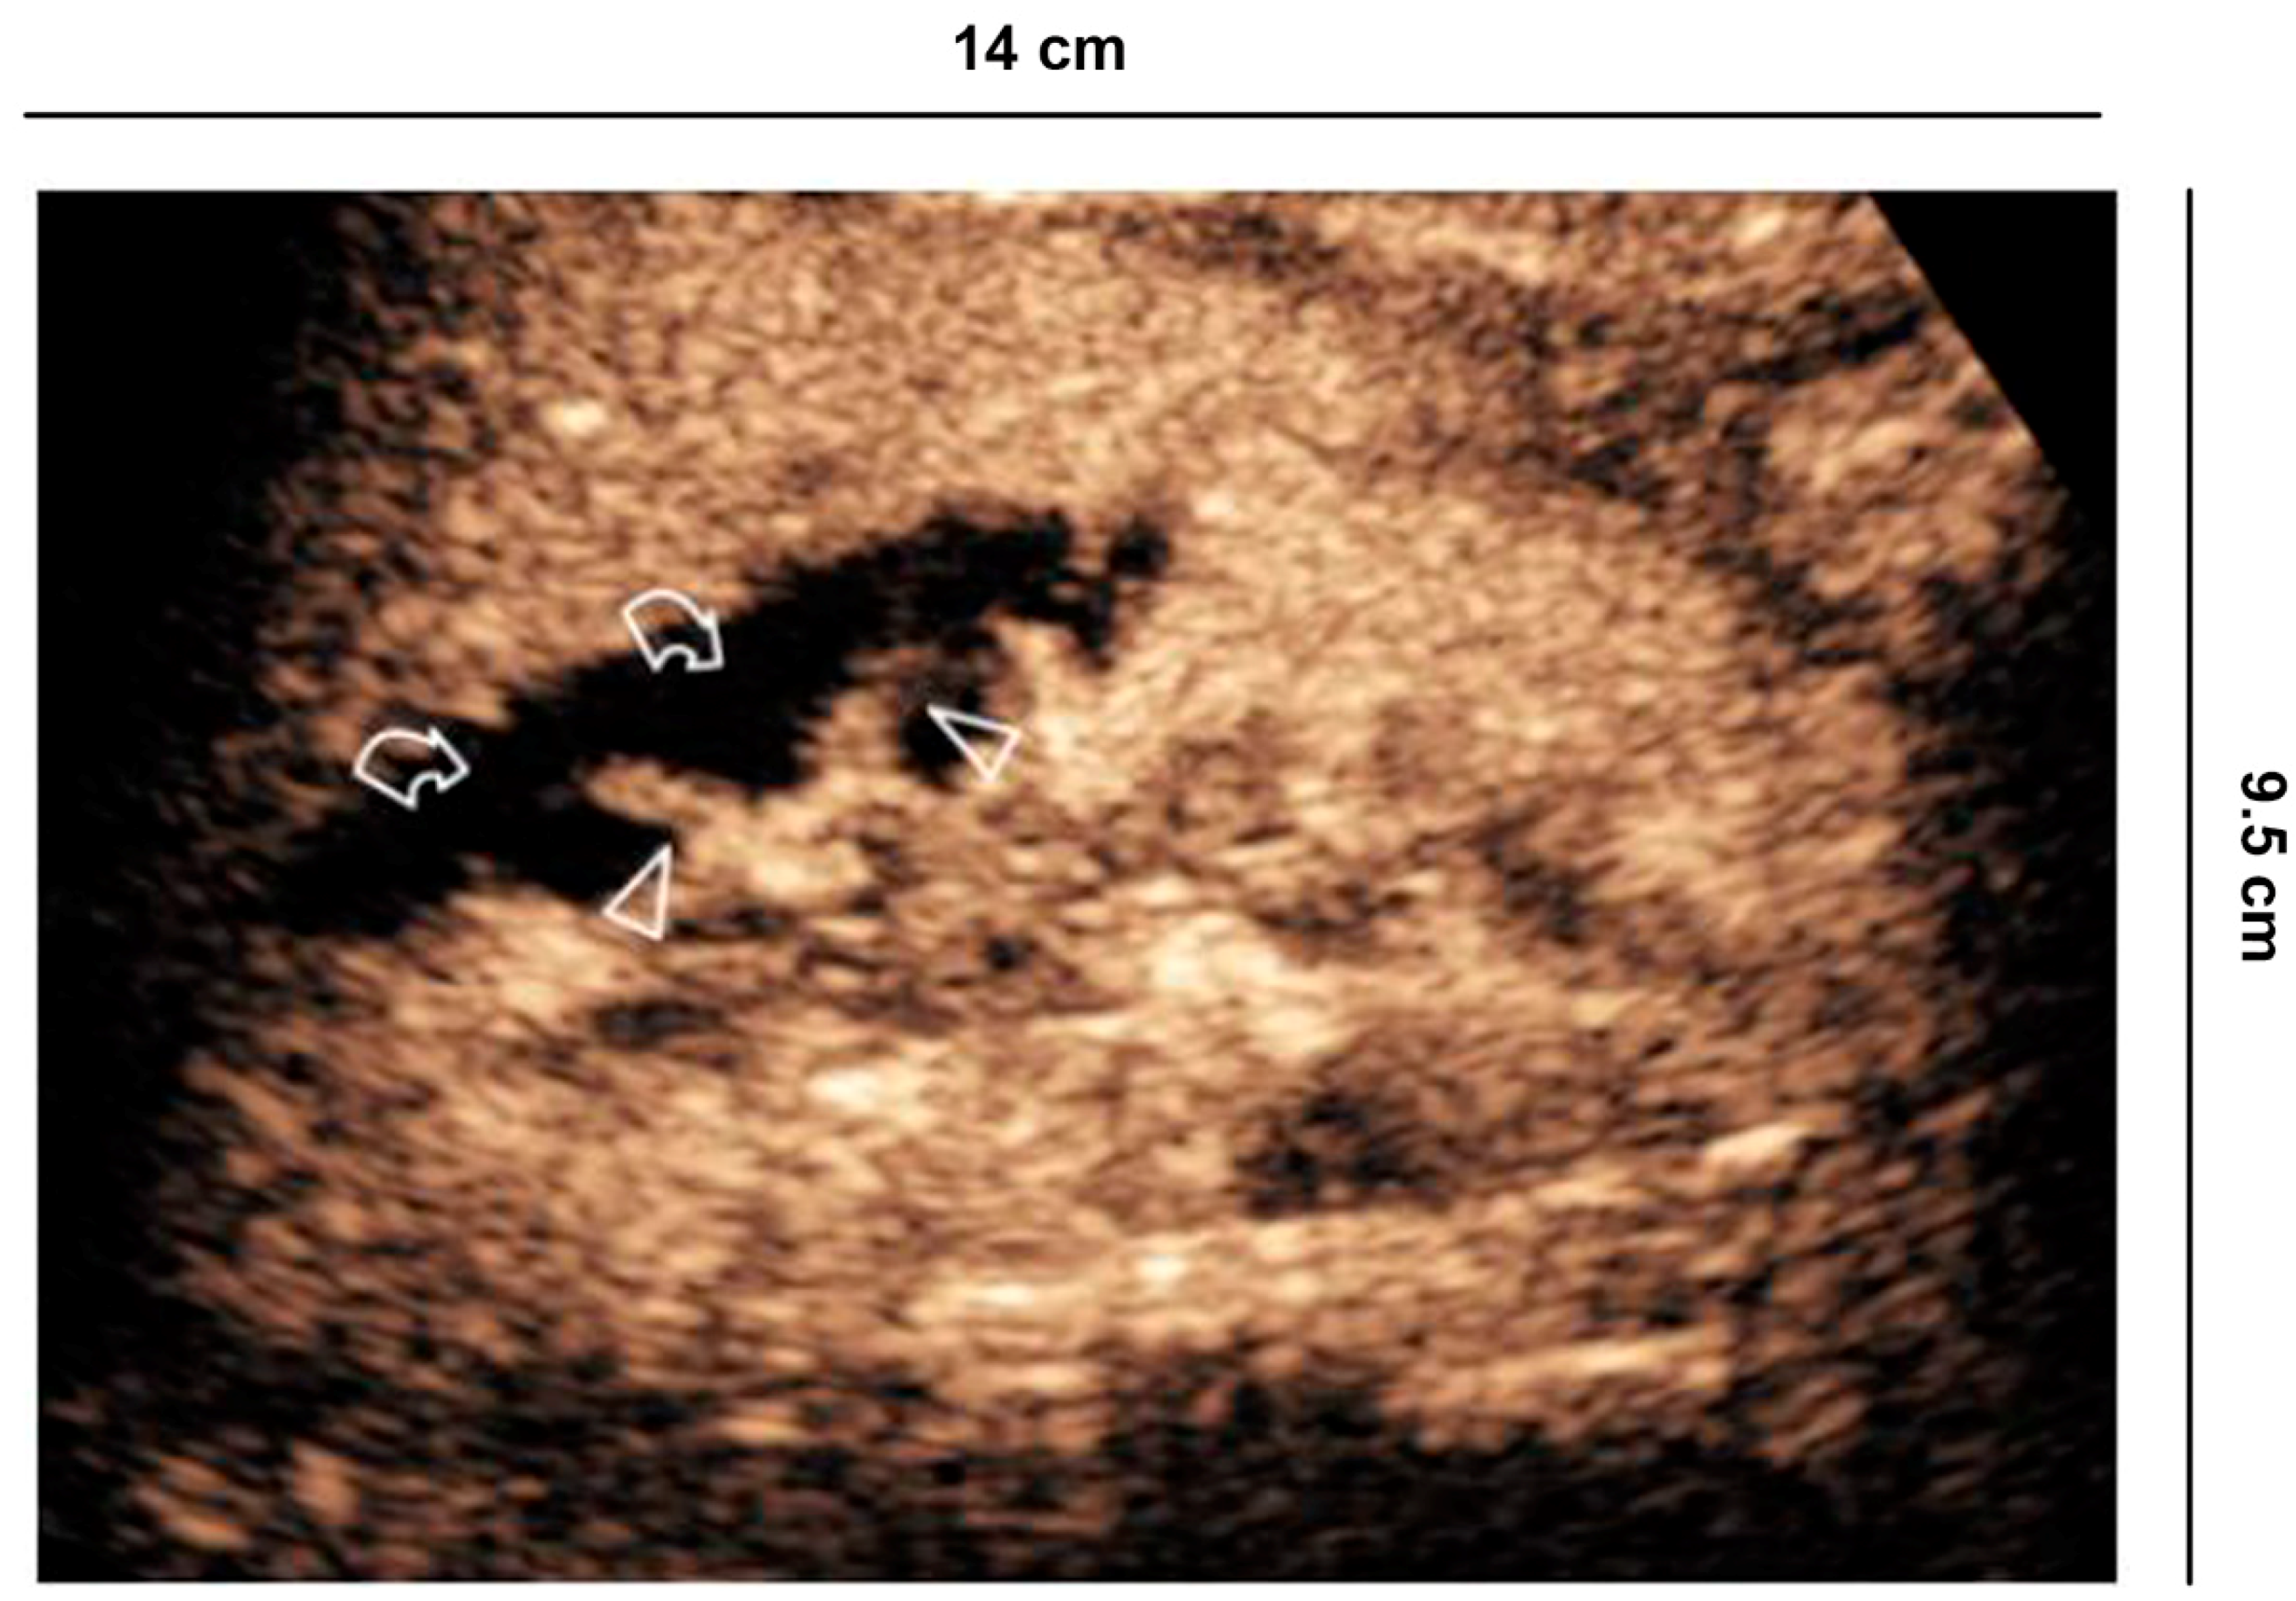

Renal infarction (often in triangular form) or only cortical ischemia (absence of cortical interlobular vessels) (Figure 8) [,] are recognizable on the other hand with CEUS, which is able to enhance the lack of vascularization, and therefore repair the damage. The sensitivity of CEUS is quite similar to that of angiography and CT [].

Figure 8.

Vascular lesions. 56 years old man with atrial fibrillation shows creatinine elevation and right lower back pain. CEUS demonstrates focal acute cortical ischemia (curved arrow) and patent interlobar vessels (arrowheads).